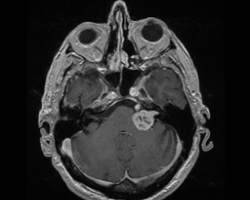

Un homme de 55 ans, n’ayant aucun antécédent personnel est envoyé pour réaliser une IRM par son ORL pour exploration d’acouphènes associés à une hypoacousie droite ainsi que des vertiges et une paralysie faciale périphérique droite d’apparition récente.